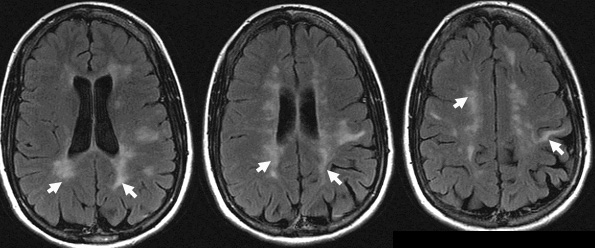

Multiple sclerosis plaques occur in the white matter of the cerebral hemispheres, brain stem and spinal cord.

They are seen as bright lesions on T2 weighted or FLAIR series MRI.

F-37 was paraparetic postpartum 6 yrs ago, with subsequent blurry left eye, then weak, numb (decreased pinprick and proprioception) and spastic right lower limb 3 yrs ago.

Nonenhanced brain MRI (FLAIR) images show asymmetrical, abnormal high signal white matter lesions in the periventricular and subcortical areas